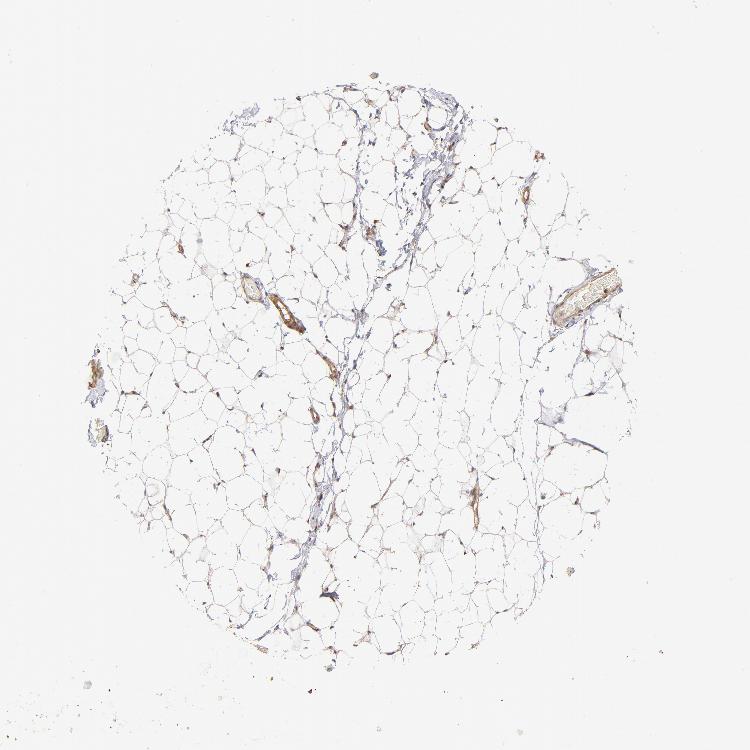

TISSUE PRIMARY DATA SOFT TISSUE Show tissue menu

SOFT TISSUE - Expression summary

SOFT TISSUE 1 - Antibody stainingi

Antibody staining in the annotated cell types in the current human tissue is reported as not detected, low, medium, or high, based on conventional immunohistochemistry profiling in selected tissues. This score is based on the combination of the staining intensity and fraction of stained cells.

Each image is clickable and will lead to virtual microscopy that enables deeper exploration of all samples and also displays staining intensity scores, fraction scores and subcellular localization as well as patient and tissue information for each sample.

Antibody HPA059297Antibody HPA069003Antibody CAB003434

Chondrocytes Not detected-Low

Fibroblasts Not detectedNot detectedMedium

Peripheral nerve --Low